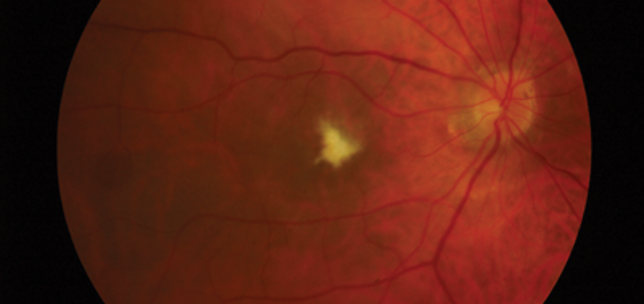

Macula re-attachment following intravitreal ranibizumab in rhegmatogenous retinal detachment

Rubina Rahman

Egle Rostron

Kamron Khan

1st February 2015